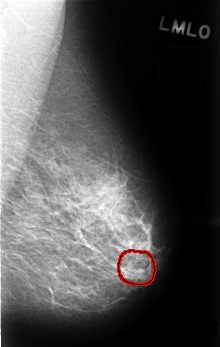

C_0487_1.LEFT_MLO

LEFT_MLO LINES 4504 PIXELS_PER_LINE 2848 BITS_PER_PIXEL 12 RESOLUTION 50 OVERLAY

FILE: C_0487_1.LEFT_MLO.OVERLAY

TOTAL_ABNORMALITIES 1

ABNORMALITY 1

LESION_TYPE CALCIFICATION TYPE PLEOMORPHIC DISTRIBUTION CLUSTERED

ASSESSMENT 3

SUBTLETY 4

PATHOLOGY BENIGN

TOTAL_OUTLINES 1

BOUNDARY